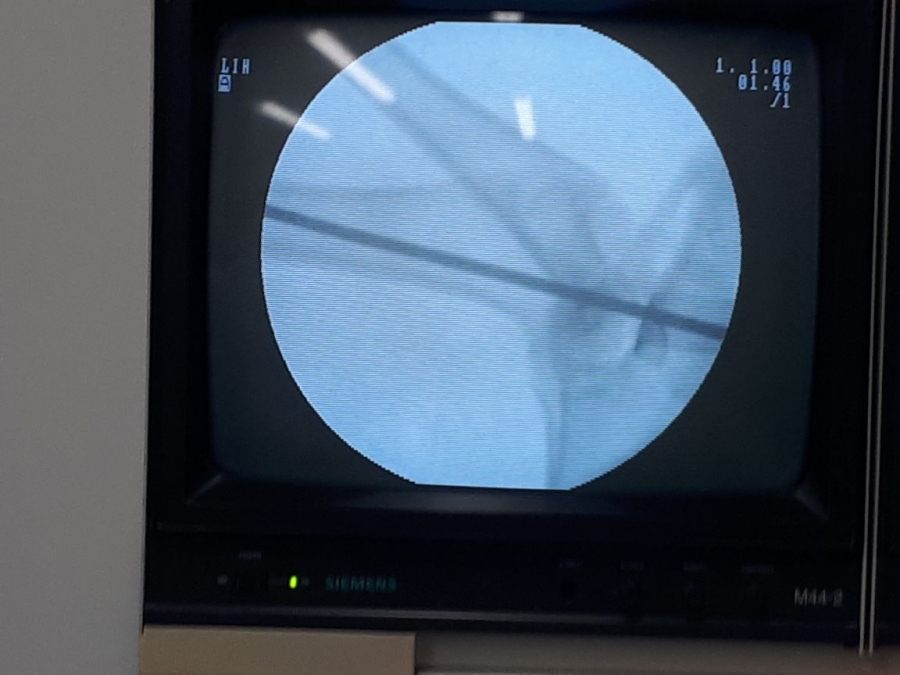

Los investigadores de la Facultad de Salud realizaron pruebas en los modelos vivos. En este caso las pruebas se realizaron en ratas con implantes subcutáneos, conejo con aplicaciones en el fémur; por último, se hicieron pruebas en cerdos, donde se realizaron implantes con resultados satisfactorios.

Las pruebas en humanos aún no se han realizado pues se esperan nuevos resultados con animales, para pasar a esta fase. Los cementos óseos son materiales empleados por cirujanos y ortopedistas para la fijación de prótesis articulares o dentales. Usualmente son dos componentes, una ampolleta de color oscuro y una bolsa estéril donde viene un componente sólido.

-Se cambiaron los componentes como el cloruro de circonio que sirven para visualizar el pegante en una radiografía, por materiales que son mejor asimilados por el cuerpo.